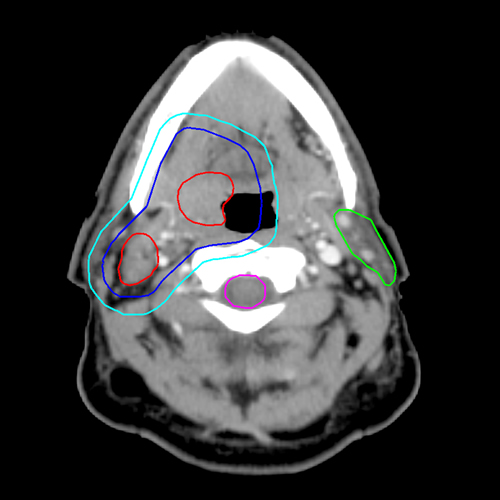

The green outline in the image above identifies which of the following?